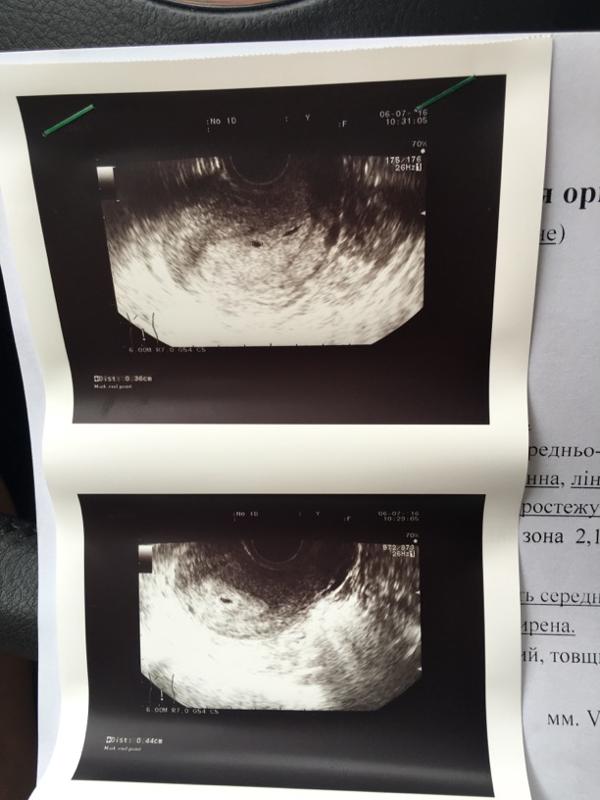

Иногда на шестой неделе беременности при трансвагинальном УЗИ можно зафиксировать биение сердца (или даже двух!). Тем не менее с какой-либо точностью о присутствии второго ребенка можно будет говорить только после УЗИ на 12-й неделе.

Для диагностики различных состояний, врачи часто используют УЗИ. Будущей маме предстоит регулярно проходить такое обследование. Именно этот метод позволит узнать, сколько малышей находится в матке. Стоит выяснить, когда можно определить двойню по УЗИ. Специалист может увидеть количество эмбрионов примерно в 5-6 недель. Но по разным причинам на маленьком сроке устанавливают, что в матке несколько плодов, не всегда. В ряде случаев врач точно диагностирует этот факт позже, например, во время скрининга в первом триместре.

С большой вероятностью двойня на УЗИ заметна после 5-ти недель, если совершается передвижение зародыша по направлению к матке и визуализируется два черных пятнышка. Обследование по УЗИ назначает личный гинеколог, если сможет заметить активный рост объемов матки. Чтобы узнать про наличие монозиготных плодов УЗД визуализирует их не ранее 12 месяцев. В данный промежуток времени у зародышей разделились пальчики на обеих руках, сформировывались пуповины и развивается 1, 2 плаценты. Исследование происходят систематически (ежемесячно) для своевременного распознавания присутствия/отсутствия патологий. Увидеть развитие двух плодов согласно диагностике на ранних сроках весьма затруднительно из-за специфик положения и особенностей УЗД техники (новейшие устройства имеют наиболее высокие возможности к точному осмотру).